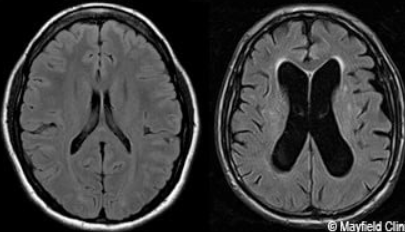

What is hydrocephalus, and what does it look like on CT head?

Hydrocephalus: Abnormal accumulation of CSF in brain ventricles and spinal cord

CT finding: Ventricles look swollen with loss of sharp points, with dark colour (hypodense due to fluid accumulation)

Which conditions cause hydrocephalus?

Blockage in CSF flow: Spina bifida, tumour, traumatic brain injury, meningitis

Impaired CSF absorption: Stroke, medications